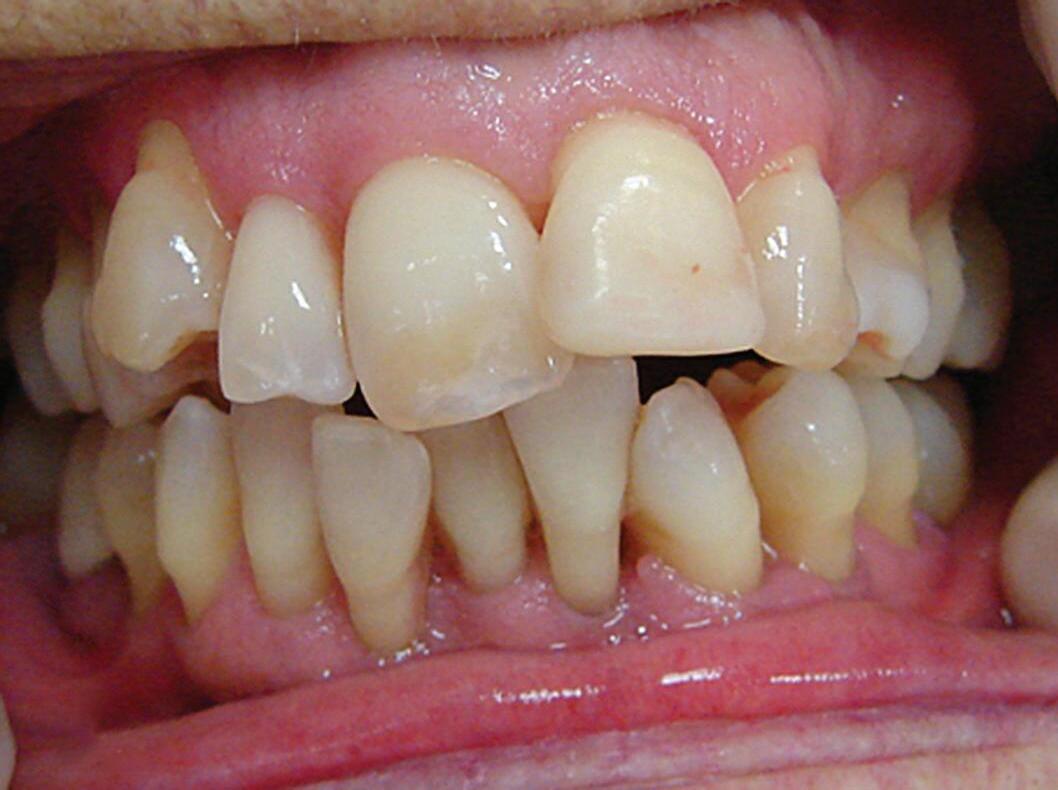

Fig. 20-1. hábitos bucais durante a vida interferem na saúde bucal dos idosos no último ciclo vital. (a) Paciente de 78 anos, gênero feminino, apresentando retrações gengivais, cemento exposto, maloclusão e apinhamento dentário – fatores que dificultam a higiene bucal. ao longo da vida, conseguiu manter a saúde periodontal. (b) Paciente de 78 anos, gênero masculino, apresentando retrações gengivais, cemento exposto, dentes em posições razoavelmente adequadas. entretanto, os hábitos de higiene acabaram por comprometer a saúde bucal. a b